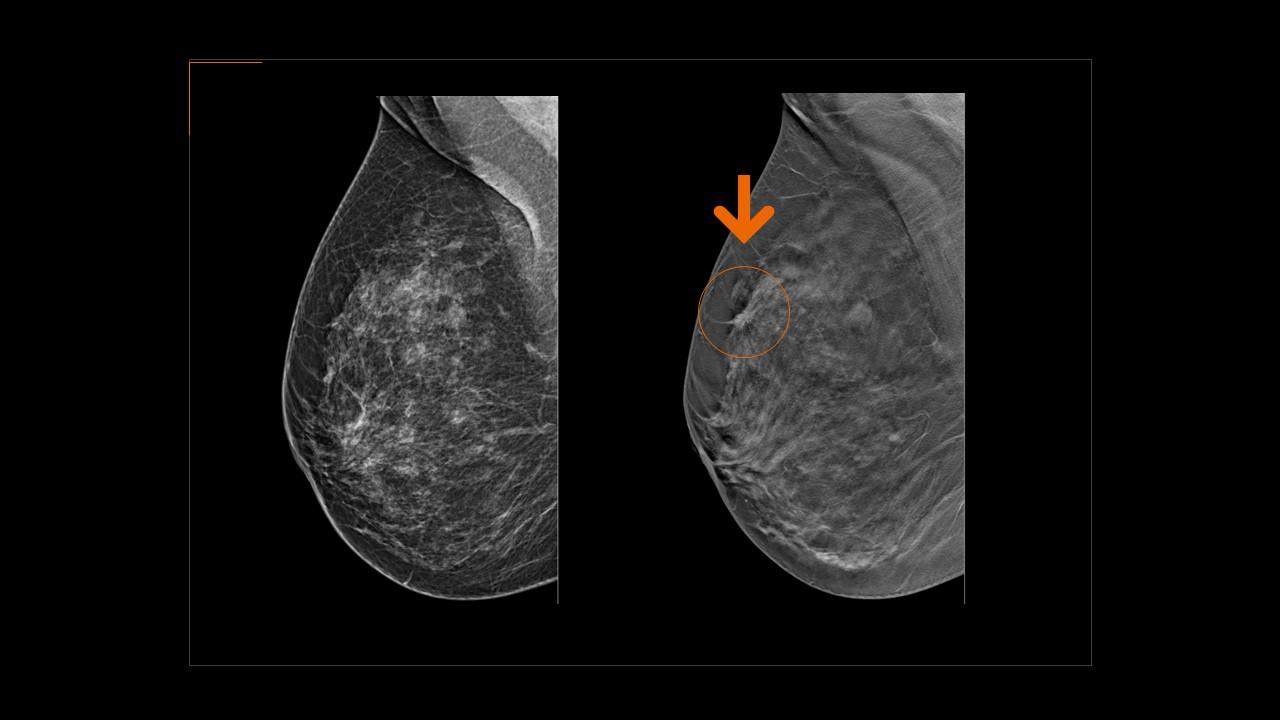

- Clinical application of contrast-enhanced mammography with real-life case studies

- Workflow and pitfalls of contrast-enhanced mammography

Current Clinical Practice and Future Directions in Contrast-Enhanced Mammography

Contrast-Enhanced Mammography in Practice: Workflow, Protocol, and Pitfalls